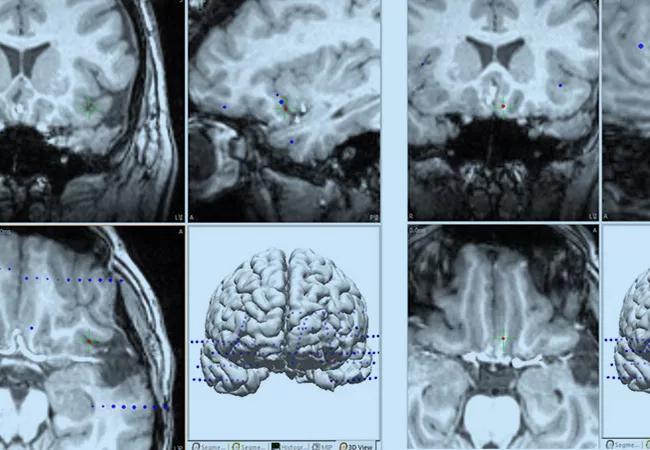

Figure 4c. Three-dimensional reconstruction showing electrode trajectories (blue dots) and the location of contacts with high epileptogenicity (red dots) in the insular-opercular region (top left), posterior orbitofrontal region (top right), superior temporal gyrus/temporal operculum (bottom left) and right hippocampus (bottom right).

The patient underwent a laser ablation procedure in January 2014 in the left orbitofrontal region and the left anterior insula (Figure 5). During immediate postoperative follow-up, she reported an improvement, with reduced frequency and severity of seizures. No side effects from the procedure were reported.

Inset Fig-5

Figure 5. MRIs showing tailored laser ablation performed in the left posterior orbitofrontal region (top images) and left insular-opercular region (bottom images).